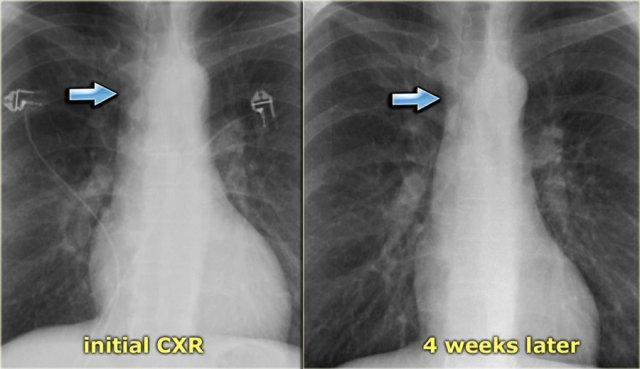

Bên trái là hình ảnh một bệnh nhân với các dấu hiệu kín đáo của suy tim sung huyết trên phim X-quang ngực ban đầu (hình 1/2).

Cuống mạch máu hơi giãn rộng, điều này trở nên rõ ràng hơn khi so sánh với phim X-quang ngực sau điều trị bằng thuốc lợi tiểu (hình 2/2).